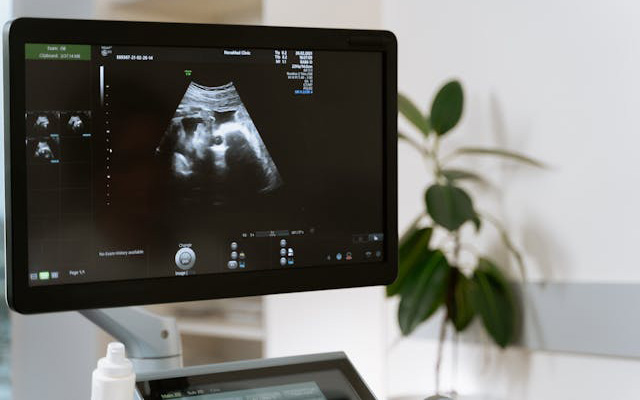

التصوير بالموجات فوق الصوتية في أمراض النساء والتوليد

فحص غير مؤلم لرؤية الرحم والمبايض أو لمتابعة تطور الحمل، مع دقة وأمان.